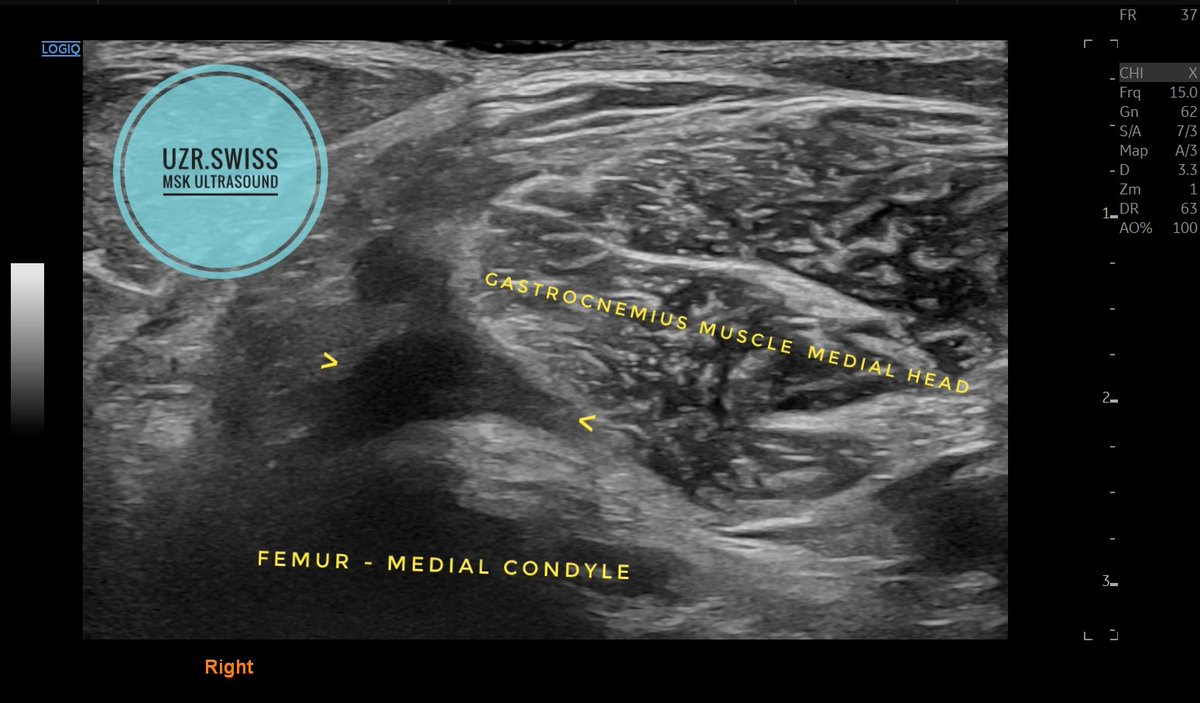

SONOANATOMY

Hɪɢʜ-ʀᴇsᴏʟᴜᴛɪᴏɴ ᴀᴛʟᴀs

Mᴜsᴄᴜʟᴏsᴋᴇʟᴇᴛᴀʟ ᴜʟᴛʀᴀsᴏᴜɴᴅ, ɴᴇʀᴠᴇ ᴀɴᴅ sᴘɪɴᴀʟ ᴜʟᴛʀᴀsᴏᴜɴᴅ,

ᴀʀᴛʜʀᴏsᴄᴏᴘʏ ᴀᴛʟᴀs ᴀɴᴅ ᴜʟᴛʀᴀsᴏᴜɴᴅ-ɢᴜɪᴅᴇᴅ ɪɴᴛᴇʀᴠᴇɴᴛɪᴏɴs.

Iɴ ᴀᴄᴄᴏʀᴅᴀɴᴄᴇ ᴡɪᴛʜ ɢʟᴏʙᴀʟ sᴛᴀɴᴅᴀʀᴅs, ᴡᴇ ʜᴀᴠᴇ ɪɴᴄʟᴜᴅᴇᴅ ʜɪɢʜ-ʀᴇsᴏʟᴜᴛɪᴏɴ ɪᴍᴀɢᴇs ᴏғ ᴍᴜsᴄᴜʟᴏsᴋᴇʟᴇᴛᴀʟ ᴜʟᴛʀᴀsᴏᴜɴᴅ sᴏɴᴏᴀɴᴀᴛᴏᴍʏ ɪɴ ᴏᴜʀ ᴛᴇxᴛʙᴏᴏᴋ.

Including:

- Over 2000 pictures

- The normal musculoskeletal tissues' ultrasound patterns

- Arthroscopic and anatomical Images

- Using guidelines from SGUM, EULAR, EFSUMB, DEGUM, OEGUM, ESSR, and SSIPM

- Ultrasound techniques for guided injection

- Ultrasound of nerves and the spine

- Methods for spinal and specific nerve injections

- Point-of-Care Ultrasound (POCUS) - Emergency ultrasound

- Vascular sonoanatomy in GCA

- Salivary Glands Ultrasound